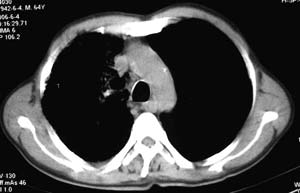

右侧胸廓略小于左侧,右肺上叶大片实变影,近肺门处密度较高,内见支气管气相,周围较淡,呈网格状,余肺野清晰,纵隔内见肿大淋巴结,右侧胸腔少量积液。临床 咳血,咳痰 发热 , 血象1.2万。

考虑大叶性肺炎。

鉴别,细支气管肺泡癌,弥漫性可有病变侵犯一个肺叶,呈炎性实变,密度偏高,可见支气管气相、蜂窝状气腔,与本例影像上不易鉴别,但临床多为咳嗽、咳白色泡沫痰,感染症状轻。